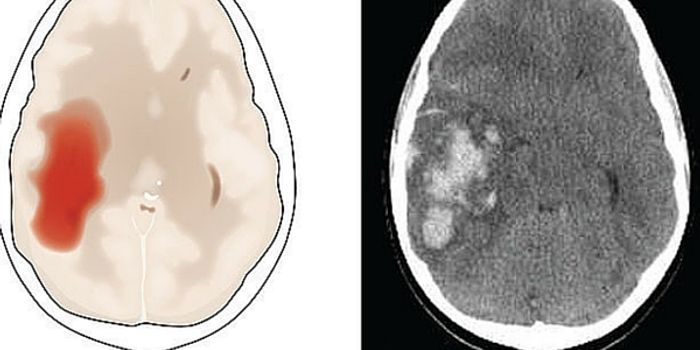

MAY 04, 2016NeuroscienceRupture of small blood vessels in the brain can cause hemorrhagic stroke and brain microbleeds, and finding the fastest ...

APR 27, 2016NeuroscienceStroke is the fifth leading cause of death in the US and the leading cause of both short and long-term disability. ...

MAR 21, 2016NeuroscienceThe most common kind of stroke, an ischemic stroke, is caused by a blood clot which blocks the flow of oxygenated blood ...

JAN 28, 2016NeuroscienceWhen a patient suffers a stroke, the key factor is time. Neurologists call it a Golden Window where “time is brain ...